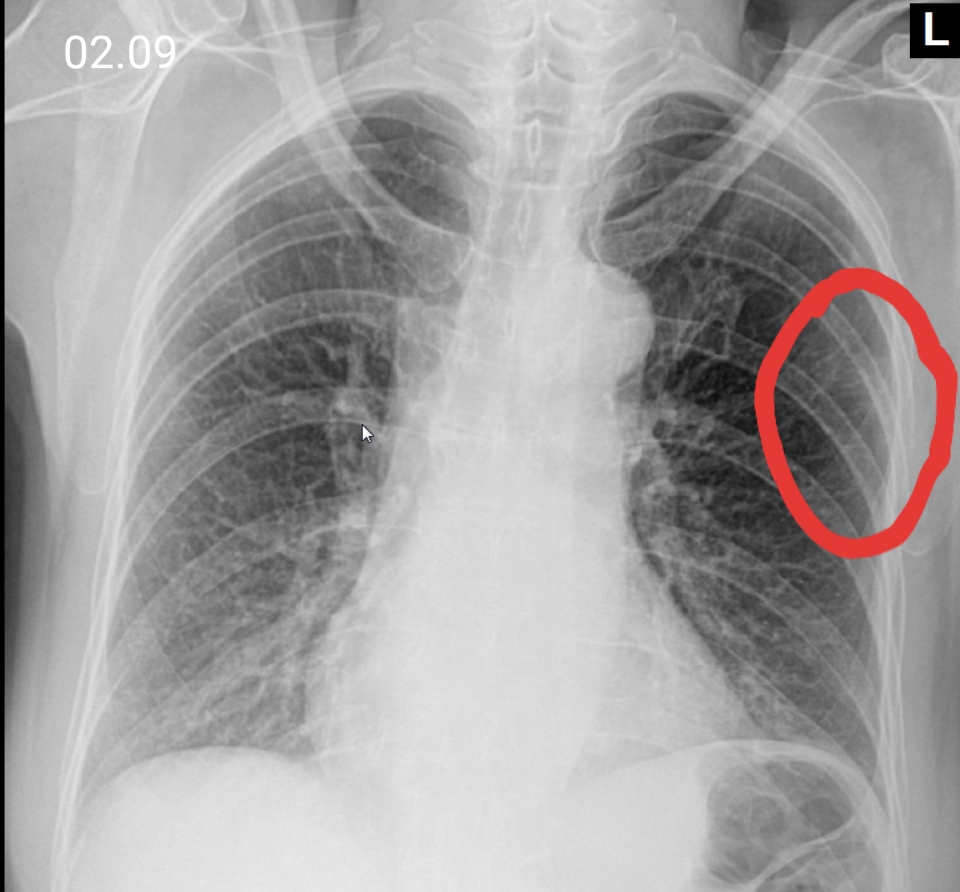

Симптомы туберкулеза: Как распознать и что делать

Раздел: Визуальные уроки